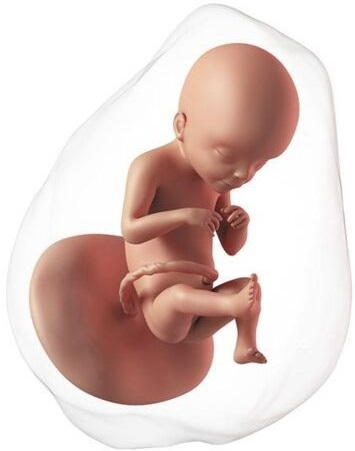

El proceso de la formación del embrión está ya prácticamente finalizado con una longitud de 30 mm. A partir de ahora empieza la etapa fetal, médicamente ya no es un embrión sino un feto. Ya ha completado la formación básica de todos los sistemas.

Ahora ya se mueve con frecuencia, pero son movimientos involuntarios; los músculos todavía tardarán en estar conectados con el cerebro. La cabeza es mucho más grande que el cuerpo, ya tiene orejas, nariz, hasta los párpados, los cuales estarán fusionados durante semanas. Los labios están formados y empieza a abrir la boca. Ya han aparecido pies y manos.

En esta etapa los genitales son exactamente iguales en niños y niñas. Tienen un tubérculo genital que más adelante se diferenciará en la forma de cada sexo. Su piel es translúcida, se puede ver el esqueleto a través de ella. En realidad, los huesos no tienen casi calcio, están formados por cartílago, pero la mayoría de los huesos ya tienen su forma definitiva.